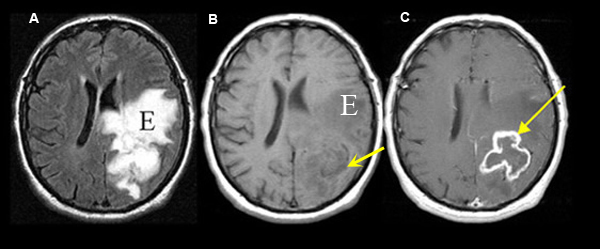

Figure 1

A: Axial flair MRI

B: Pre-contrast axial T1 wtd. image

C: Post-contrast axial T1 wtd. image

Imaging findings: Figure 1

- An irregular enhancing ring lesion (arrow in C) is seen involving the left parietal lobe in post-contrast axial T1 wtd. MRI, but poorly visible on pre-contrast T1 wtd. image (arrow in B).

- Tumor is associated with edema (E) and better noticed on FLAIR image (A), compared to T1 wtd. image (E in B)

Final impression:

Glioblastoma involving the left parietal lobe.